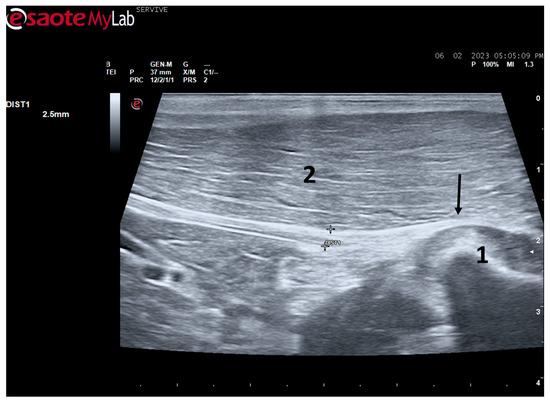

Figure 4.

Ultrasound image of the left sciatic nerve of a sheep nerve halfway through the thigh: (1) sciatic nerve, identified by an arrow (nerve fascicles enclosed by perineurium); (2) epineurium, identified by an arrow; (3) biceps femoris muscle; (4) piriformis muscle; (5) adductor muscles. DIST1 represents the measurement of the diameter of the sciatic nerve halfway through the thigh.

At the level of the stifle, and with great interindividual variation, the two branches of the sciatic nerve, the common peroneal nerve, and the tibial nerve, are easily observable and distinguishable, diverging from the main nerve (Figure 5). Both the sciatic nerve and its branches appear as hypoechogenic neuronal tubular structures (nerve fascicles and the perineurium) surrounded by a hyperechogenic envelope corresponding to the connective tissue nerve wrappings (epineurium) (Figure 3, Figure 4 and Figure 5). The most lateral nerve, appearing dorsally on the ultrasound image, corresponds to the common peroneal nerve and imagiologically has a slightly smaller diameter than the tibial nerve, which is more medial and appears ventrally on the ultrasound image. Accompanying both nerves distally, there is a tendency for a slight decrease in their diameter before the final ramifications, but the intended site for inducing injury to the common peroneal nerve is proximal to the point where the decrease in diameter occurs.

The sciatic nerve was easily identified mid-thigh medially to the biceps femoris muscle and caudal to the femur and vastus lateralis muscle, allowing these muscles to be used as reference points for quick identification even for less experienced ultrasonographers. Monitoring the nerve in a proximal direction makes it possible to identify its passage between the greater trochanter of the femur and the ischial tuberosity, and these bony projections can be used as a reference point for its location. More proximally is its emergence from the greater sciatic foramen. At this level, the nerve may be more difficult to identify due to its curvature and also due to its proximity to the caudal gluteal artery and vein, but the use of a color-flow Doppler may clear up any doubts. Confusion with the sacred loin trunk in this region will be more unlikely since it is at greater depth. The sciatic nerve can also be easily tracked distally to the point where it branches proximally to the stifle. As the nerve progresses, an increase in echogenicity seems to be observed, a phenomenon described in other species [16], and which is probably related to an increase in the connective tissue within the nerve. It is important to remember that this increase in the amount of connective tissue is also related to an increased likelihood of compression or stretching injuries, making it harder to observe the nerve and apply local anesthetic blocks [26]. The mean diameter of the sciatic nerve measured mid-thigh and just before its branching site is identical to that indicated in other species, such as dogs of similar size. Its ultrasound appearance is similar to that described in other species, such as humans [27], dogs [14,15], or cats [16], appearing as a hypoechogenic tubular structure covered by a hyperechogenic envelope corresponding to the epineurium, an aspect that allows its easy differentiation from soft tissues and bones in the vicinity. Before its branching site, the sciatic nerve diameter was also measured in a cross-section, rotating the probe 45 degrees from the position that allows for obtaining the longitudinal image (Figure 8). Obtaining an image in this plane proved to be more complex and made it difficult to establish anatomical relationships with neighboring structures and with the ramifications of the sciatic nerve. On the other hand, the ultrasound image reveals characteristics identical to those obtained in the regular plane, in addition to the measured diameter being the same as that obtained with the previous technique. Therefore, it was decided not to use the transverse plane for this ultrasound characterization in any of the considered nerves.